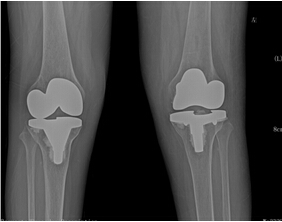

來(lái)院后,骨科二區(qū)唐雄主任、廖浩主治醫(yī)師熱情接待了她。經(jīng)查,患者為嚴(yán)重的類風(fēng)濕性關(guān)節(jié)炎導(dǎo)致的雙膝關(guān)節(jié)破壞,雙膝關(guān)節(jié)內(nèi)翻畸形并嚴(yán)重的骨質(zhì)缺損,同時(shí)由于患者長(zhǎng)期服用激素類藥物,其全身骨質(zhì)均有嚴(yán)重的骨質(zhì)疏松?;颊叩弥∏閲?yán)重性后,感到失望、沮喪,唐雄主任信心滿滿地安慰道,“您這種情況行膝關(guān)節(jié)置換術(shù),就能徹底解決關(guān)節(jié)疼痛和雙膝關(guān)節(jié)不能活動(dòng)的問(wèn)題?!庇谑牵∪擞种匦氯计鹆藢?duì)生活的希望,并要求盡快進(jìn)行手術(shù)治療。

考慮到患者為長(zhǎng)期慢性病病人,唐雄主任決定先給患者疼痛程度更高的右側(cè)膝關(guān)節(jié)進(jìn)行手術(shù)治療。經(jīng)過(guò)完善備血、調(diào)整激素用量等術(shù)前準(zhǔn)備后,2015年10月10日,唐主任為患者進(jìn)行了右側(cè)膝關(guān)節(jié)人工關(guān)節(jié)置換術(shù),術(shù)后患者恢復(fù)良好。右側(cè)膝關(guān)節(jié)疼痛解除,術(shù)后3天右下肢能下地活動(dòng)。出院后,患者對(duì)右側(cè)膝關(guān)節(jié)置換術(shù)的效果非常滿意。 2016年7月17日,唐主任為該患者再次進(jìn)行了左膝關(guān)節(jié)人工關(guān)節(jié)置換術(shù)?;颊咝g(shù)后3天就能下地活動(dòng)。現(xiàn)在她的臉上又出現(xiàn)了燦爛的笑容,她逢人就說(shuō),要是早一點(diǎn)來(lái)手術(shù)治療,就能早一點(diǎn)擺脫病痛的折磨了。